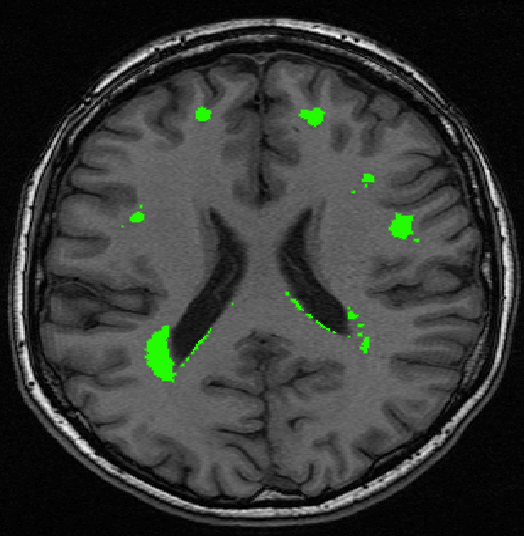

We use images from three different studies (see Fig. 1 for examples of slices):

10 MS patients from the MS Lesion Challenge [11] scanned at the Children’s Hospital of Boston (CHB), scanned with T1, T2 and FLAIR at 0.50.50.5mm resolution.

10 MS patients from the MS Lesion Challenge [11] scanned at the University of North Carolina (UNC), scanned with T1, T2 and FLAIR at 0.50.50.5mm resolution.

- 3.

Here again the differences between study populations influence the class priors. On average, the percentage of voxels that are lesions are 1.6%, 2.6% and 0.2% in CHB, RSS and UNC respectively. The differences between subjects also vary: these are relatively small for CHB and UNC, but very large for RSS. In RSS, the subject with the least lesion voxels has only 0.08%, while the patient with the most lesion voxels has 14.3%.